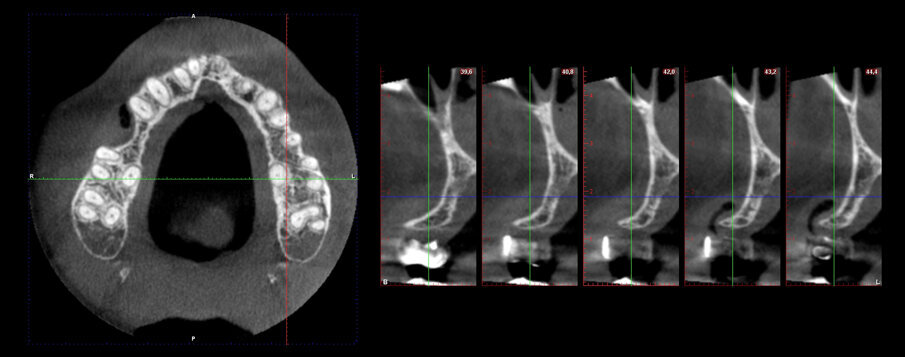

Caso clinico Viene presentato un caso clinico di GBR per la ricostruzione volumetrica di una cresta ossea atrofica mascellare con inserimento di biomateriale osseo di natura eterologa (OsteoBiol Gen-Os) e di una lamina corticale soft collagenata (OsteoBiol Lamina Soft) stabilizzata sulla sede del difetto osseo con utilizzo di colla di fibrina (Tisseel, Baxter) e con 2 chiodini di fissazione crestali. La paziente N.H. di anni 42, sesso femminile, non fumatrice, ASA 1, si presentò alla mia osservazione per la sostituzione di un elemento dentale, 2° premolare superiore destro, estratto più di 15 anni prima (Figg. 2, 3). Dall’esame clinico si osserva un marcato riassorbimento in senso orizzontale del sito edentulo, lo stato dei tessuti gengivali è di salute, non vi sono lesioni parodontali sui denti contigui. L’esame CBCT conferma la perdita di oltre il 50% del tessuto osseo vestibolare pur rimanendo conservata l’altezza verticale della cresta (Fig. 4).

Fig. 4 - Forte perdita ossea vestibolare.